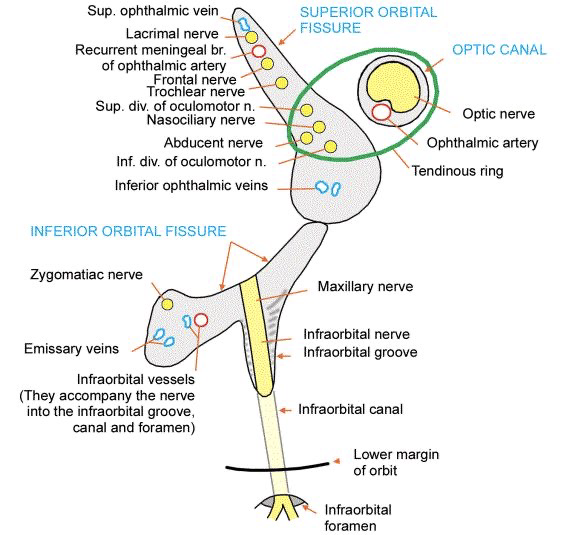

| CN | Origin | foramen |

|---|---|---|

| I | 嗅球 | cribriform plate |

| II | Optic Chiasma | optic canal |

| III, IV | Midbrain | sup orbital fissure |

| V1, VI | pons | |

| V2 | foramen rotundum | |

| V3 | foramen ovale | |

| VII | Internal coustic meatus | |

| VIII | Pons, Medulla 之間 | |

| IX, X, XI | Medulla | jugular foramen |

| XII | Hypoglossal canal |

Sphenoid bone

-

pterygoid hamulus

-

Foramen rotundum

-

Foramen ovale

-

Foramen spinosum

-

Pterygoid canal

-

Foramen lacerum (破裂孔)

-

Optic canal

- CN II

- Ophthalmic a.

-

Sup. orbital fissure

- Ophthalmic n.(CN V1)/ v.

- CN III, IV, VI

Temporal bone

- Carotid canal

- Ext. acoustic meatus

- Int. acoustic meatus

- CN VII, VIII

- Jugular foramen

- int. jugular v.

- CN IX, X, XI

- Stylomastoid foramen

- Foramen lacerum

- Petrotympanic fissure